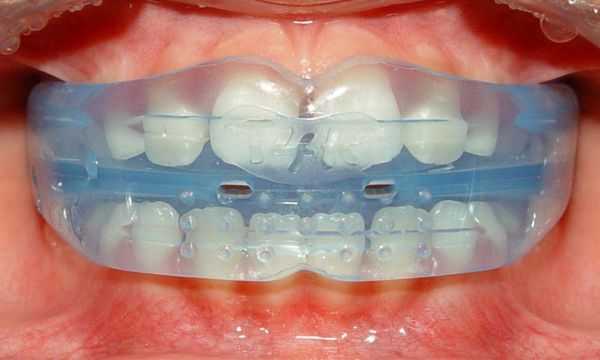

Учитывая хорошую форму зубных рядов, отсутствие выраженной скученности, торто-аномалий, лечение начато с установки дуги Cu-Ni-Ti (0,17x0,25). Уже через два месяца достигнута конгруэнтность зубных рядов, сопоставляющихся в конструктивном соотношении со множественными окклюзионными контактами.

Тем не менее мы сочли возможным проведение операции при установленной в полости рта Cu-Ni-Ti-дуге. У этой пациентки прослежены наиболее отдаленные результаты из выборки пациентов, у которых применялся такой план лечения (3,5 года ретенции). А именно ненадежность достигнутого соотношения челюстей являлась одним из аргументов оппонентов данной методики.